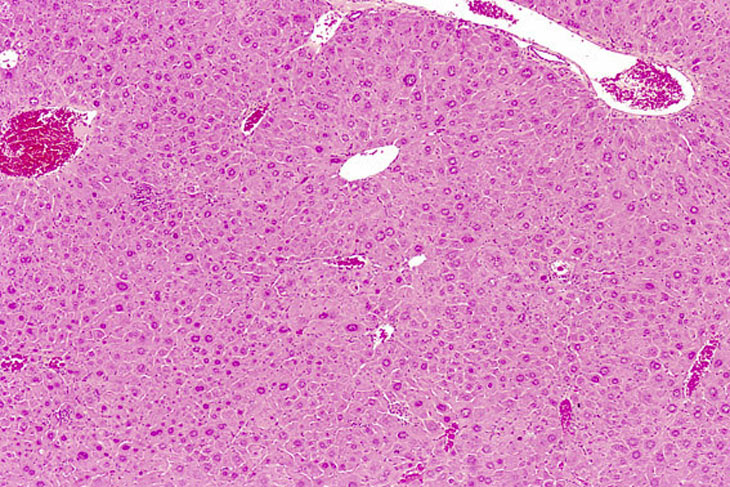

Hepatocellular hypertrophy is frequently seen in the liver following exposure to agents that cause hepatic enzyme induction. The hypertrophy typically starts in the centrilobular area and extends to the mid-lobular and eventually periportal areas provided there is sufficient stimulus over time. In situations of prolonged exposure to some agents, the hypertrophic hepatocytes are seen to have enlarged polyploid nuclei. With some treatment regimens, hepatocytes may actually become cytomegalic. Cytomegalic hepatocytes typically have single polyploid and/or multiple nuclei.

Generalized hepatocyte hypertrophy involving all portions of the hepatic lobule. Higher magnification shows a cytomegalic hepatocyte in the lower right. It has an enlarged nucleus with multiple nucleoli.

Hypertrophic and cytomegalic hepatocytes are present in the centrilobular and midlobular areas in these images from a mouse treated with chlordane for several months. Some cytomegalic hepatocytes have several nuclei.